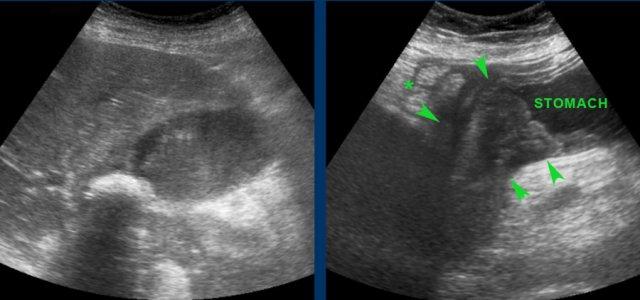

Hình ảnh siêu âm của một bệnh nhân bị phình to túi mật cấp tính, được khảo sát trên mặt phẳng dọc và mặt phẳng ngang.

Sỏi gây tắc nghẽn đang ở trạng thái kẹt (mũi tên).

Lưu ý rằng khi ấn đè, túi mật phình to phồng lên về phía thành bụng (đầu mũi tên), cho thấy áp lực trong lòng túi mật tăng cao.